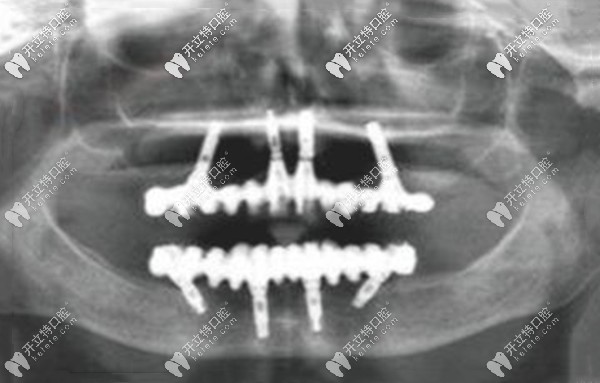

從上圖可以看出,高先生的滿口只剩下兩顆“搖搖欲墜”的牙齒,牙槽骨明顯能看出來吸收、萎縮,高度明顯降低;這就是之前假牙脫落的真正原因。

爾睦口腔肖步挺醫(yī)生對高先生的口內(nèi)拍CT片檢查后,評估了牙槽骨的厚度、密度、高度、上下頜的咬合關(guān)系,為其設(shè)計了目前比較先進的All-on-4全口咬合重建的種植牙方案。

allon4即刻負重種牙,也就是上、下頜各植入4顆植體(兩顆純直植入、兩顆傾斜植入),再搭配覆蓋義齒,就能發(fā)揮全口的咬合力,而且是當天種、當天戴臨時牙冠、當天就能吃東西。

深圳沙井爾睦口腔肖步挺院長給高先生做的allon4全口種植牙,全程用的是數(shù)字化種植方式,傷口比較小、安全性也高,比較適合老年人的半口及全口無牙的情況~~~